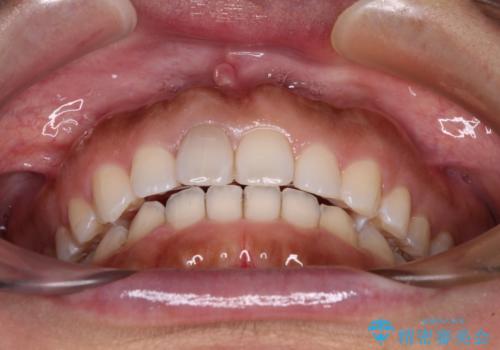

隙間の空いた前歯を閉じたい インビザライン矯正

- 前歯の隙間を気にして来院された患者様です。

隙間、捻転ともに軽微でありましたが、下顎前歯の突き上げにより隙間ができていたため、インビザラインを用いて咬み合わせを改善しながら前歯の歯列を整えていくこととしました。

当初は1年程度で終えられると思いましたが、治療途中から装着時間が短くなったり、来院間隔が長期になったりとし、結果として4年半以上の治療期間となりました。

治療途中に上顎前歯は失活してしまいましたが、変色が顕著ではないため、経過を見ていくこととなりました。